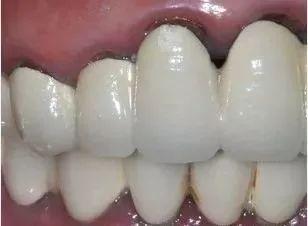

不知何时起,烤瓷牙已经风靡一时,受到很多人的追捧,但在追捧的同时,很多人都对烤瓷牙可谓是又爱又恨,最初烤瓷牙可以帮助缺损的牙齿得到修复,有了它缺损牙齿变完整了似乎也有些变美了,每次微笑都能够展现出自信的笑容。但是时间久了,有部分的人的烤瓷牙开始变了,一点点露出黑色的牙龈线,还有一些人的烤瓷牙甚至产生崩坏的现象,甚至还产生了更为严重的口腔疾病,很多人在烤瓷牙"变质"期间由爱生恨。

然而受人追捧的烤瓷牙为什么会出现这种现象呢?其实这是由于早期做的烤瓷牙技术并不完善,早期烤瓷牙的内冠材料大多采用金属材料,在烤瓷牙的内部这种金属是不易透光的,光线不能在烤瓷牙的内部很好的折射到达烤瓷牙颈部,时间一久,便产生暗淡发黑的情况。除此之外,部分廉价的烤瓷牙材质因具有金属化学性质不稳定而产生发黑的状态。同时还跟医生的技术有关,如果技术不到位,烤瓷牙没有完美契合牙龈留有缝隙,那么就会产生磨损牙龈,产生黑线,使得烤瓷牙变质。